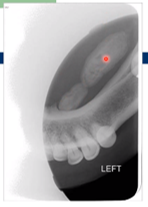

Describe what you see in this radiograph

• Presence of two large submandibular sialolith extending from duct orifice to mandibular molars